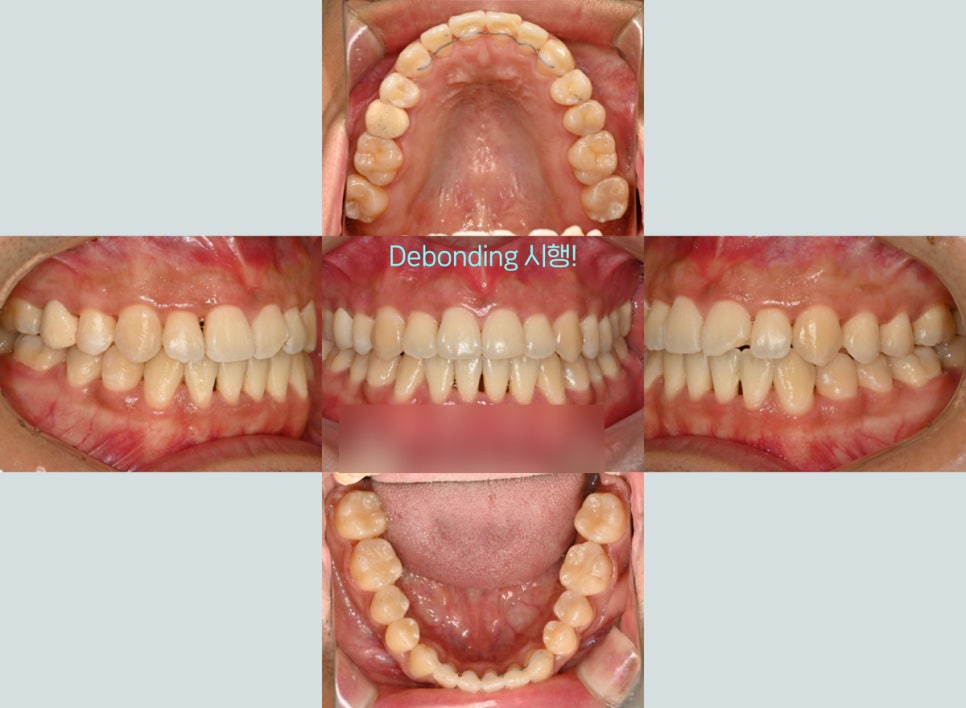

모든 과정이 완료되어 고르게 바뀐 치열을 보면

이전 모습이 생각나지 않을 정도로

심미적인 모습을 갖게 되었습니다ㅎㅎ

삐뚤어진 치아로 고민을 갖고 계셨던 분인데,

정중선도 잘 맞고 전체적으로 고른 치열을

얻게 되었네요.

고정식 유지 장치 부착 후 모든 과정을 마쳤습니다.